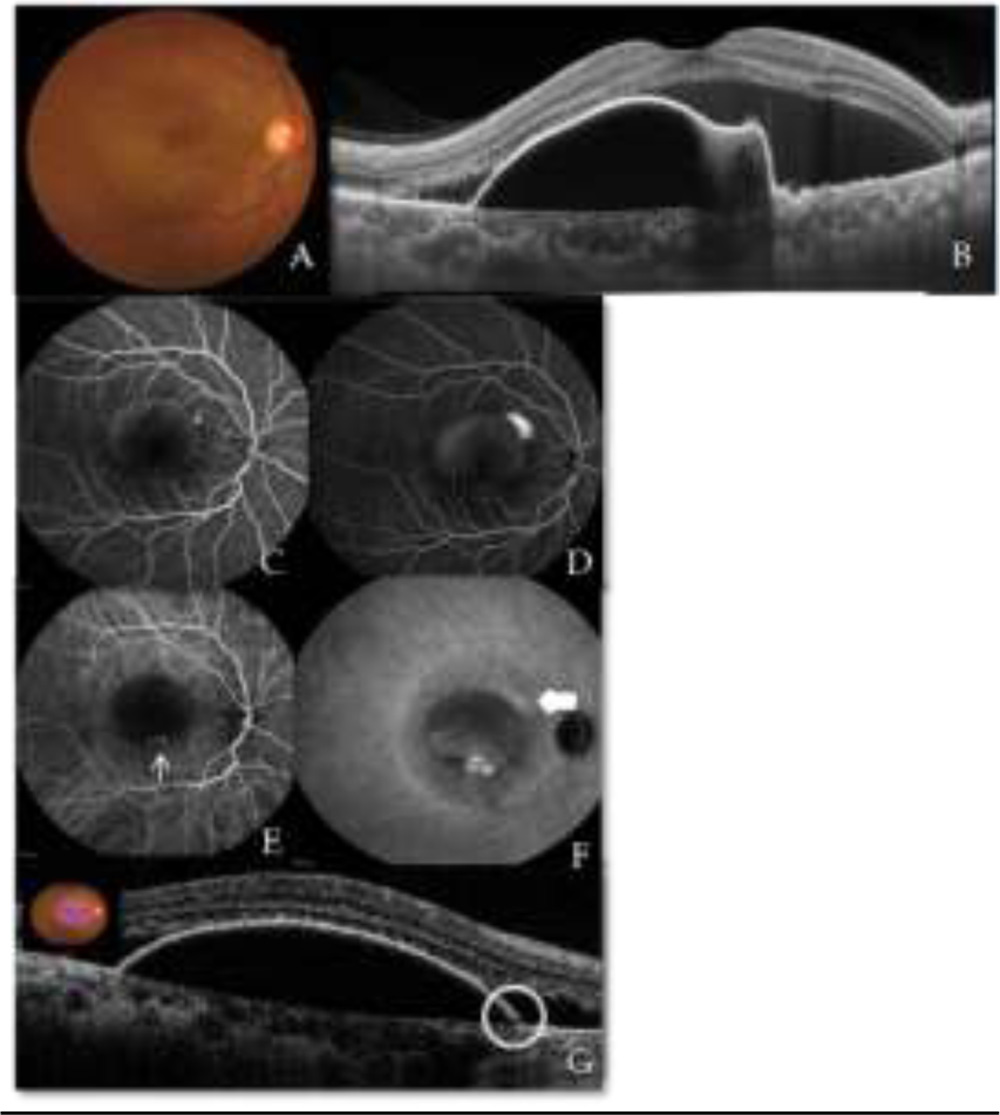

A 52 year old female presented with the complaint of defective vision in Right eye (RE) for the past 6 months. She had history of injury in the left eye (LE) in childhood following which the eye had become phthisical. On examination, her BCVA in RE was 6/18. Anterior segment was within normal limits. Fundus examination revealed large amount of SRF almost extending from superior to inferior arcade vessels with a speck of SRH (Figure 1 A). OCT revealed a large, tall and notched PED; with a polyp beneath the undersurface of RPE and SRF. Enhanced depth imaging (EDI) revealed a thick choroid with subfoveal choroidal thickness (CT) of 406µm with dilated outer choroidal vessels (Figure 1 B). On FFA, smoke stack leak was noted superonasal to fovea(Figure 1 C,D) and ICGA revealed bunch of polyps inferior to fovea along with choroidal hyperpermeability in late phase corresponding to site of CSR leak (Figure 1 E,F). On reviewing the OCT, a micro RPE rip was also noted in the region corresponding to the CSR leak on FFA (Figure 1 G).

Figure 1 Case 1 A) Colour fundus photograph of RE showing subretinal fluid(SRF) with subretinal haemorrhage(SRH) B) EDI OCT image showing notched PED with SRF with subfoveal choroidal thickness(CT) of 406µm C) FFA early stage and D) FFA late stage showing a smoke-stack leak superonasal to fovea with gradual filling of dye in PED and a stippled hyperfluorescence inferior part of the PED E) ICGA early phase and F) ICGA late phase showing a bunch of polyps(thin arrow) in area of stippled hyperfluorescence and choroidal hyperpermeability(thick arrow) in late phase at the site of CSCR leak G) Micro RPE rip(circle) in area corresponding to smoke-stack leak